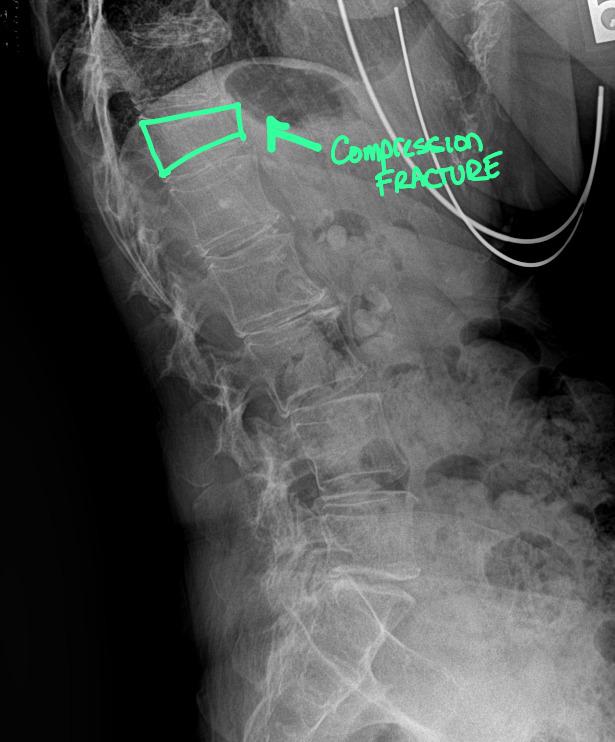

Compression Fracture: Radiology for Chiropractors, Imaging Centers, and Legal Teams Introduction A 64-year-old woman presents with acute lower back pain